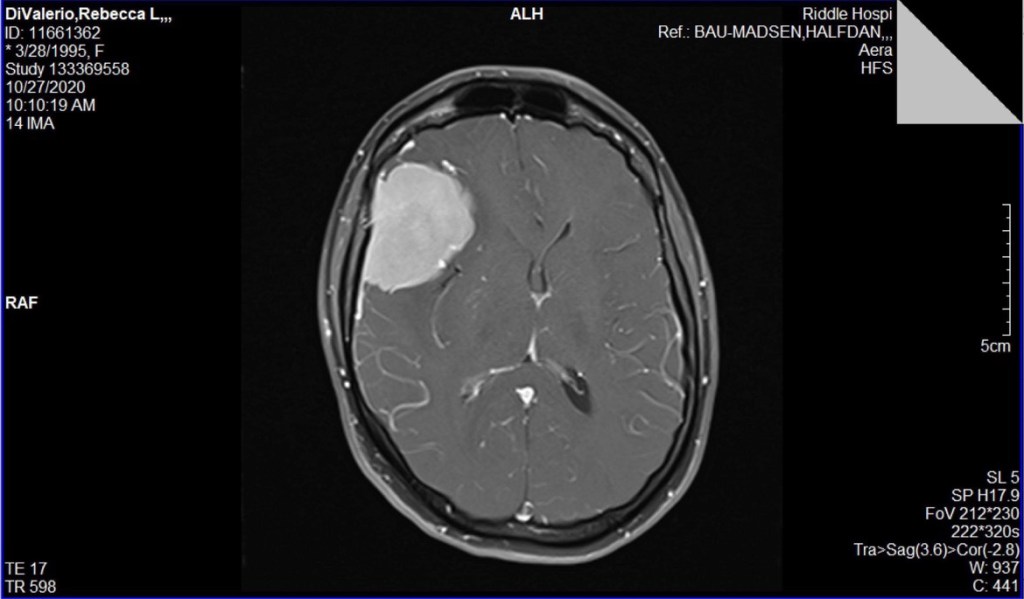

This journey embarked on October 27th, 2020. These experiences are shared through raw, transparent and vulnerable lenses. You are invited to walk the journey beside Becca.

- AlarmingNovember 2nd, 2020 An hour and a half from surgery 5:00AM, My alarm starts beeping on my phone. I roll over to silence it. There was… Read more: Alarming